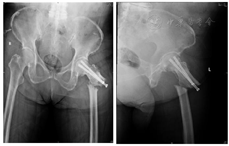

5.2017年9月双髋关节正侧位片X线片 显示左侧股骨粗隆下骨折术后1年半,侧位片仍可见清晰骨折线,正位片提示内侧皮质鸟嘴样改变更为明显(图5)。

双髋关节正位片提示:左股骨粗隆下骨折内固定术后改变,原左侧股骨颈骨折线消失,左股骨粗隆下横行骨折线清晰,断端硬化,对位、对线可。内置物位置良好,无松动。